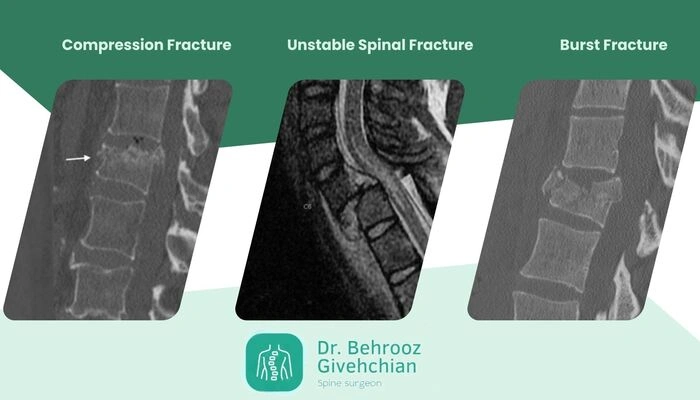

شکستگیهای پاتولوژیک که با شکستگی تروماتیک ستون فقرات میتوانند به چند شکل در ستون فقرات دیده شوند:

شکستگی فشاری (Compression Fracture): در این حالت، به دلیل ضعف ساختاری استخوان، بخش قدامی مهره تحت فشار فرو رفته و ارتفاع آن کاهش مییابد، که معمولا در بیماران مبتلا به پوکی استخوان رخ میدهد.

شکستگی انفجاری (Burst Fracture): شکستگی به گونهای است که قطعات استخوانی به اطراف و گاهی به کانال نخاعی پخش میشوند و میتوانند باعث آسیب به نخاع یا ریشههای عصبی شوند، که بیشتر در اثر تومورها یا متاستازهای استخوانی دیده میشود.

شکستگی همراه با ناپایداری ستون فقرات: زمانی اتفاق میافتد که شکستگی مهره باعث از بین رفتن پایداری مکانیکی ستون فقرات شده و امکان جابجایی قطعات و فشار مستقیم بر نخاع یا اعصاب افزایش مییابد، که خطر آسیب عصبی جدی را به همراه دارد.